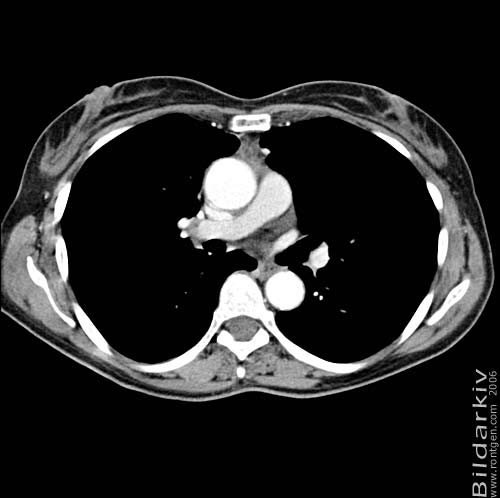

Thorax 28

Snitt över thorax med kontrast. Sk. mediastinum-fönstersättning.

Mediastinum